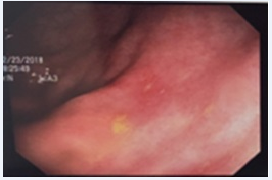

Among laboratory tests, increased levels of CA 19-9 (68.5 U/mL), normocytic and hypochromic anemia (Hb = 10.2 g/dL), besides the absence of eosinophilia, stands out. Enzymes and liver function, amylase, lipase, serologies for viral hepatitis, HIV, VDRL and fecal propaedeutic tests all within normality. Chest X-ray and abdominal ultrasonography also showed no changes. Actives duodenal bulb ulcers (Sakita's A1 classification) and partial duodenal stenosis at second duodenal portion were found in upper digestive endoscopy (Figure 1). Colonoscopy demonstrated aphthoids ulcers in descending colon (Figure 2).

Figure 1 Evidence of upper Digestive Endoscopy with active duodenal bulb ulcers (Sakita's A1 classification) and partial duodenal stenosis at second duodenal portion.

Figure 2 Colonoscopy demonstrating aphthoids ulcers in descending colon.